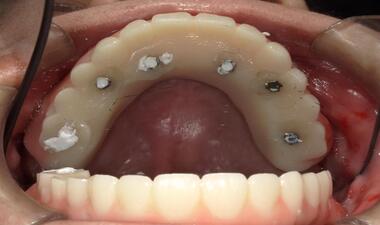

術中

上顎缺牙,植入六顆植體